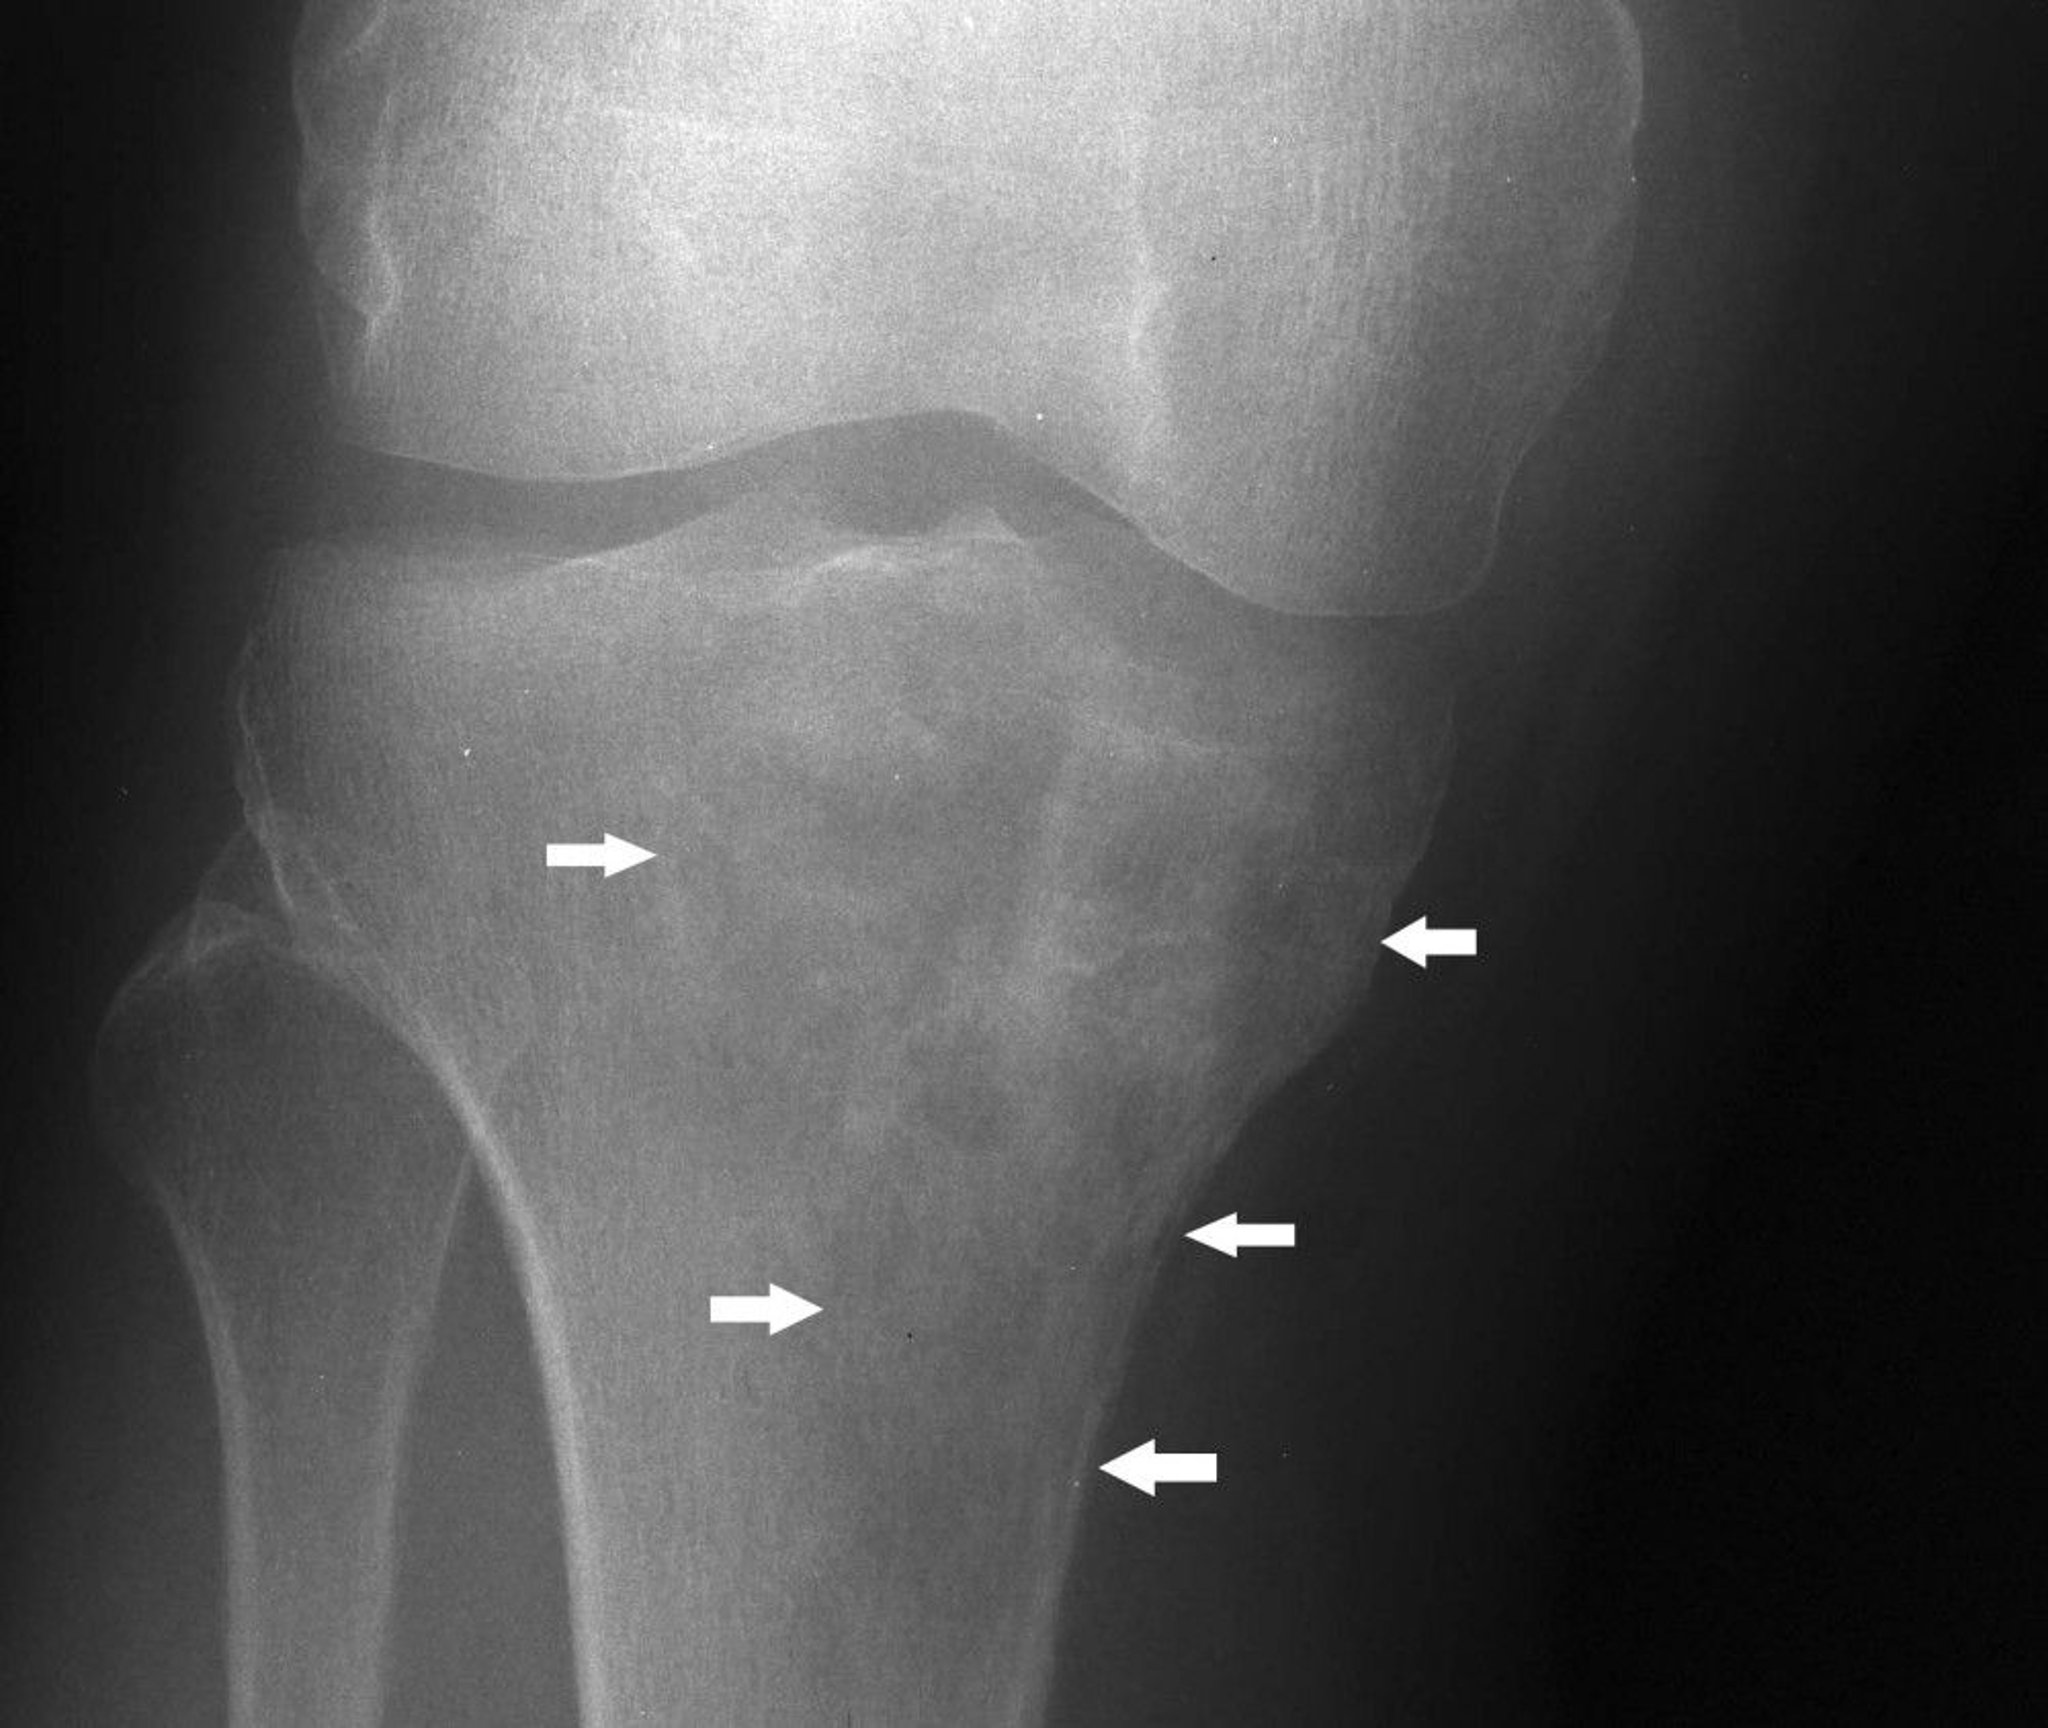

This knee radiograph shows lymphoma in the proximal tibia with a mixed lytic and sclerotic appearance below the medial tibial condyle (arrows).

Image courtesy of Michael J. Joyce, MD, and Hakan Ilaslan, MD.